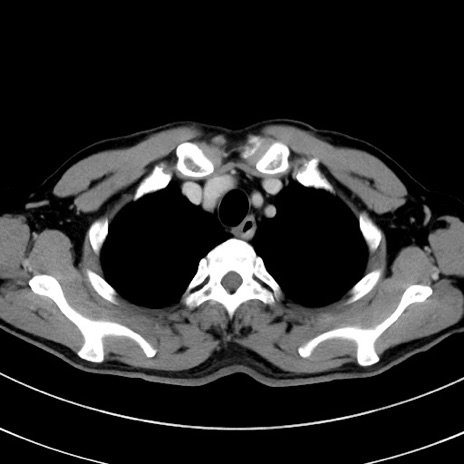

症例8(横断像)

【症例】 60歳代男性

【主訴】 黒色吐物

【現病歴】 4日前から嘔気自覚、2日前の朝食後にも嘔気あり、自分で手で嘔吐反射起こし嘔吐したところ血が混ざっていたため受診。

【既往歴】 5年前汎発性腹膜炎を伴う急性虫垂炎で手術、高血圧、前立腺肥大症、高脂血症

【身体所見】 腹部正中に手術癩痕あり 腹部平坦・軟圧痛なし膨満感あり

【データ】WBC 8400、CRP 4.54